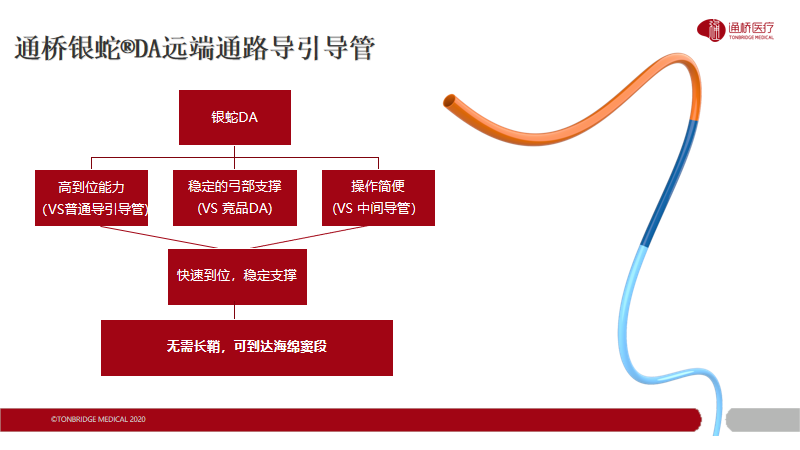

在出血手术中,我们往往会用到普通的导引导管,为动脉瘤介入栓塞提供稳定支撑。但是,对于一些远端动脉瘤或AVM,普通的导引导管因为长度和通过性受限,很难实现高到位,在一些迂曲血管中难以到达既定位置。通桥医疗通桥银蛇®DA远端通路导引导管的出现很好的解决了上述问题:105cm的长度可以实现更高到位,远端8cm柔软段提升了在迂曲血管中的通过能力,通过性能优异、支撑性能稳定。近期我科使用通桥银蛇®DA远端通路导引导管对颅内动脉瘤患者进行治疗并取得满意效果。汇报如下:

通桥银蛇®DA远端通路导引导管轻松连续过弯,到达破裂孔段。

通桥银蛇®DA远端通路导引导管轻松至海绵窦段。

用Plus导管将通桥银蛇®DA远端通路导引导管带至海绵窦段。